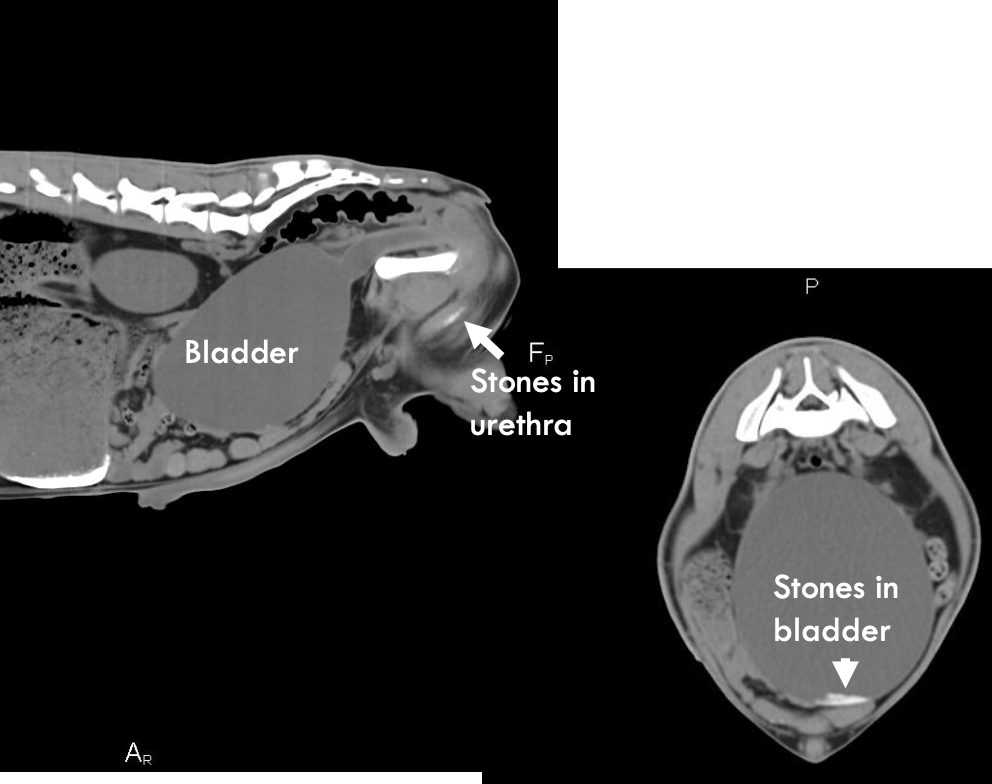

how can CT be used to identify urinary disorders in ruminants?

picks up stones, umbilical issues in calves/small ruminants (usually not cost effective)

CT scan of goat with Ca-carbonate stones in bladder

why may CT be indicated in some cases to diagnose obstructive urolithiasis?

to find missed stone, and check the bladder for stones